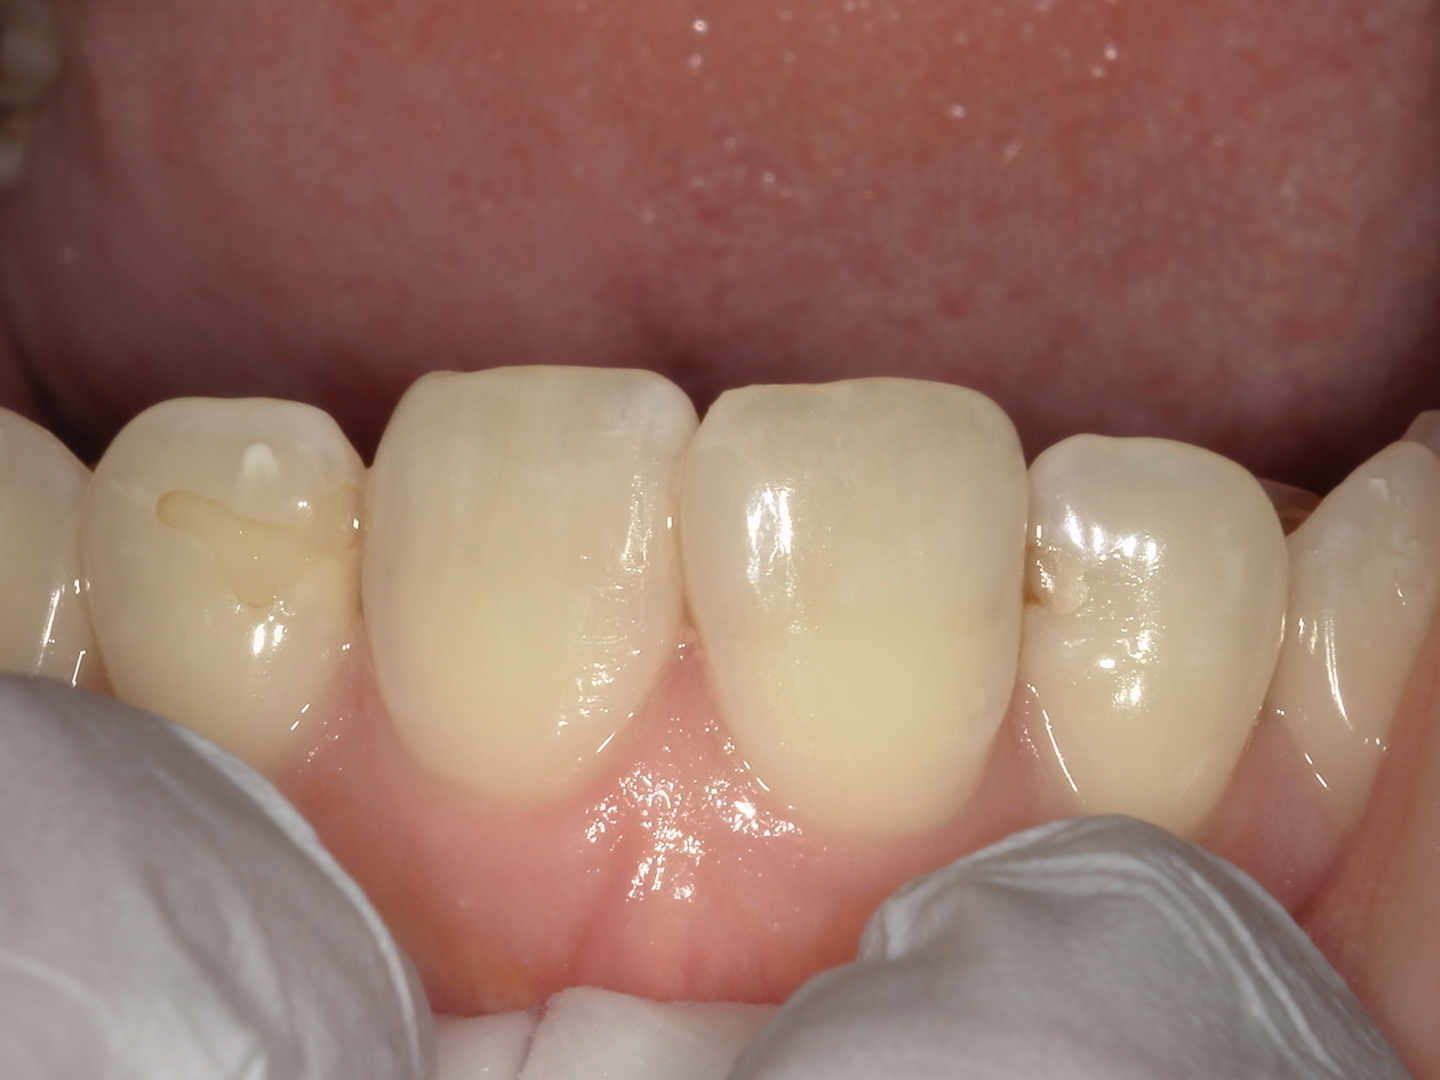

◆ 治療後の状態(After)

治療後の写真では、歯の形が自然につながり、隣接面の段差も解消されています。

色調や透明感も周囲の歯となじみ、

どこを修復したのか分かりにくい仕上がりになりました。

見た目の改善だけでなく、

-

清掃性の向上

食べ物が詰まりにくくなる

フロスがスムーズに通る

といった機能面の改善も得られています。